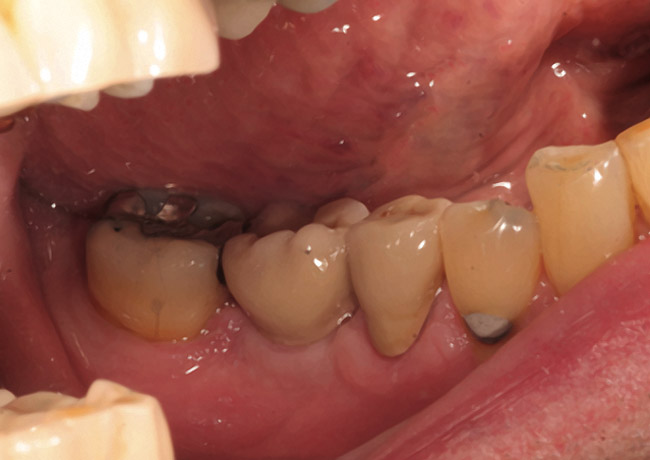

Fifteen weeks after the first procedure, the site was reopened to perform implant placement. Flap reflection revealed excellent and complete bone reformation (Figure 3). The implant osteotomy preparation was initialized with the harvest of an approximate 5-mm trephine core. The trephine had an internal diameter of 2 mm and an outer diameter of 2.7 mm. The completion of implant placement was performed according to the manufacturer's guidelines, resulting in the delivery of a 5-mm x 11-mm implant with primary stability. Because of excellent subjective stability, a transmucosal healing was chosen, with placement of a healing cap and a nonsubmerged closure (Figure 4). Qualitative histology demonstrated lamellar bone without evidence of the ACS carrier. Restorative therapy commenced approximately 4 months after implant placement. Delivery of the definitive prosthesis, consisting of a gold custom abutment and cement-retained crown, occurred at 5 months following implant placement surgery and 8.5 months after extraction and augmentation (Figure 5).